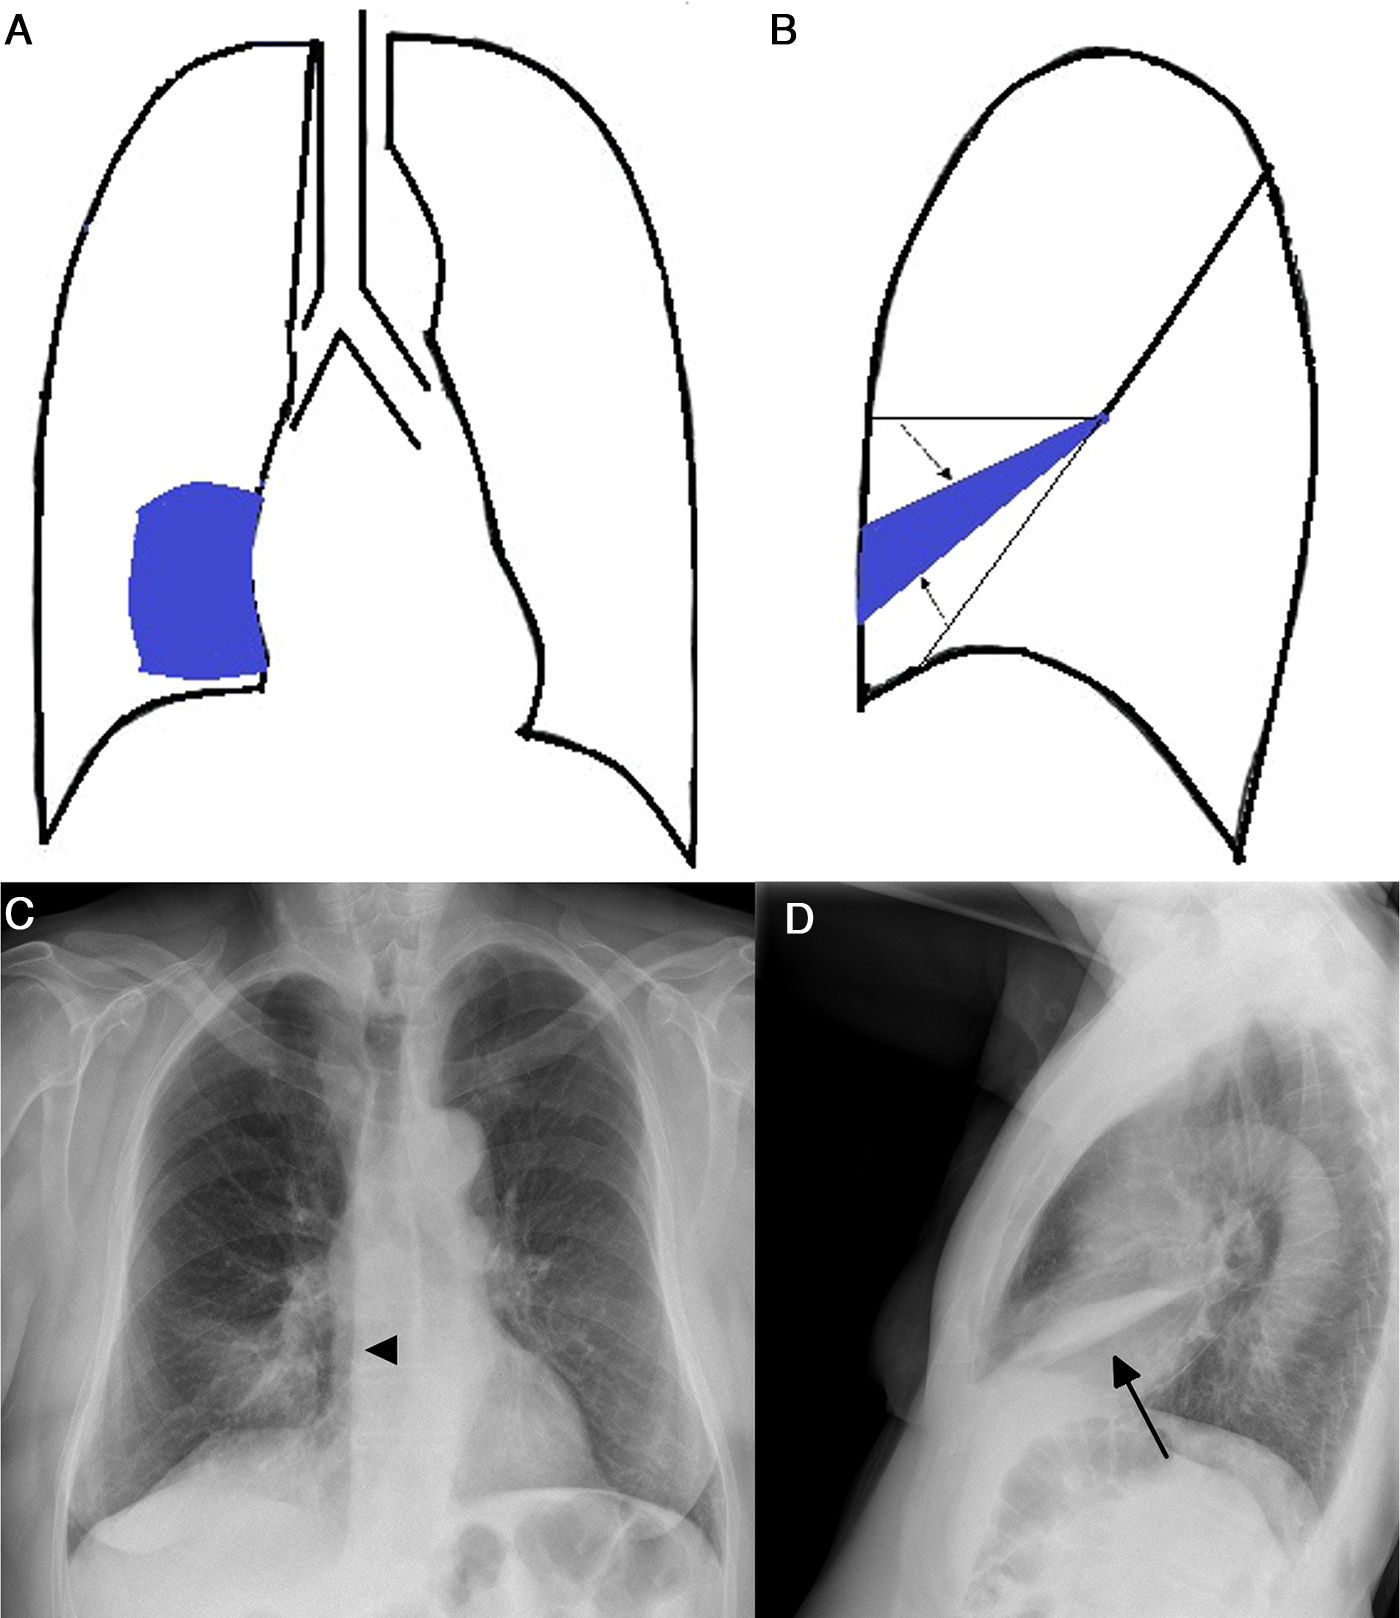

Atelectasis is an important indicator of potentially severe underlying disease that must be diagnosed as early as possible. One of the most common mechanisms is the reabsorption of air distal to respiratory tract obstruction. The chest X-ray is an excellent tool to diagnose atelectasis, and it is especially useful for ruling out central bronchial obstructions (e.g., from endobronchial tumors). If the signs of volume loss are not recognized correctly, the diagnosis and treatment can be delayed. This article describes the main findings of lobar atelectasis on chest X-rays and their correlations with CT findings, including the classic signs described in the literature and other, less known and sometimes subtle signs.